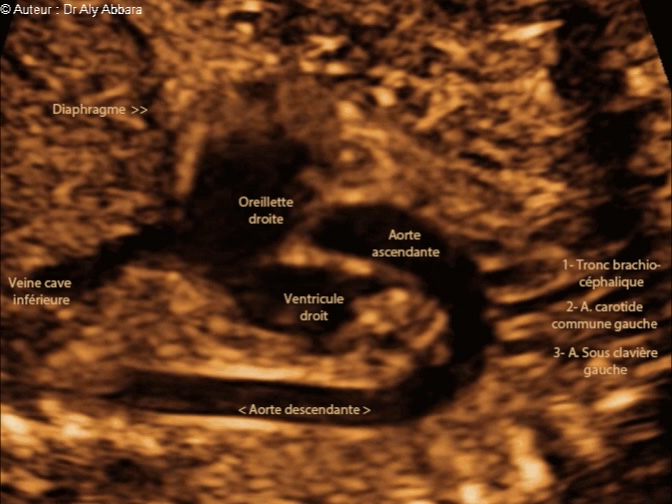

L'aorte de sa naissance du ventricule gauche jusqu'à sa portion descendante - foetus de 22 SA

Images échographiques montrant l'aorte dès son départ du ventricule gauche puis : la crosse de l'aorte avec ses trois branches (le brachio-céphalique, l'artère carotide commune gauche et l'artère sous clavière gauche) et enfin, l'aorte descendante.

Sur cette image animée on identifie également la partie terminale de la veine cave inférieure se terminant dans l'oreillette droite, puis une vue partielle de la valve tricuspide et le ventricule droit.

Foetus de 22 SA et 3 jours.